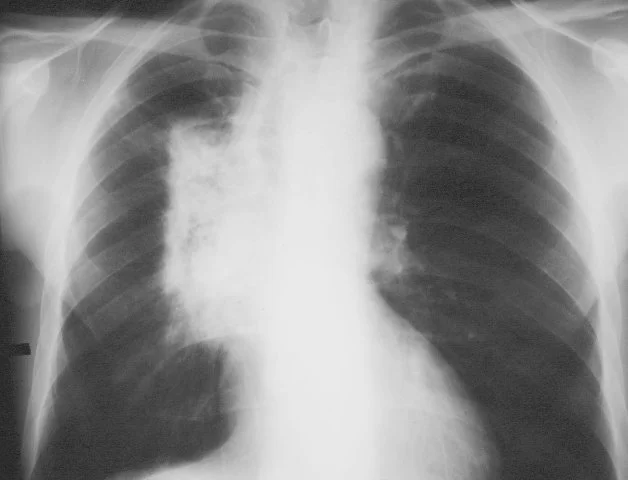

/Pneumonitis, is often confused with pneumonia, but these are similar ailments but not the same. While pneumonia is a type of infection which causes lung inflammation, pneumonitis is a general term to describe inflammation in pulmonary, or lung, tissue. So technically pneumonia would fall into the category of being a type of pneumonitis, but generally most physicians look to other causes of lung inflammation when referring to a patient having "pneumonitis." These other causes vary dramatically, from airborne irritants, to different types of cancer treatments, and even some antibiotics or aspirin. Airborne irritants are probably the most common cause of pneumonitis and can stem from being exposed to a type of chemical, dust, or bacteria.